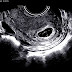

On obstetric ultrasound, the gestational sac is a dark ("anechoic") space surrounded by a white ("hyperechoic") rim.

Gestational sacs can be identified via ultrasound and are generally identified by the following 4 characteristics:

- The sac has a round or elliptical shape in longitudinal and transverse views

- it is surrounded by a white echogenic rim ("choriodecidual reaction")

- The sac is located in the uterine fundus

- The sac is not implanted on the midline, but eccentrically (to one side of the uterine cavity line).